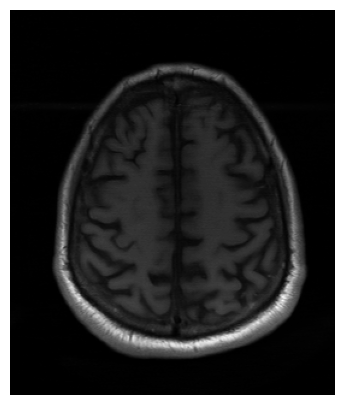

Qualitative.

The visual inspection of the images reconstructed (available in Fig. 2) at acceleration factor 4 shows little to no visible difference with the ground truth original image. However, when increasing the acceleration factor to 8, we can see that smoothing starts to appear which leads to a loss of structure as can be seen in Fig. 3.

| T1 PSNR: 38.57 SSIM: 0.9348 | T2 PSNR: 37.41 SSIM: 0.9404 | FLAIR PSNR: 36.81 SSIM: 0.9086 | T1POST PSNR: 38.90 SSIM: 0.9517 |